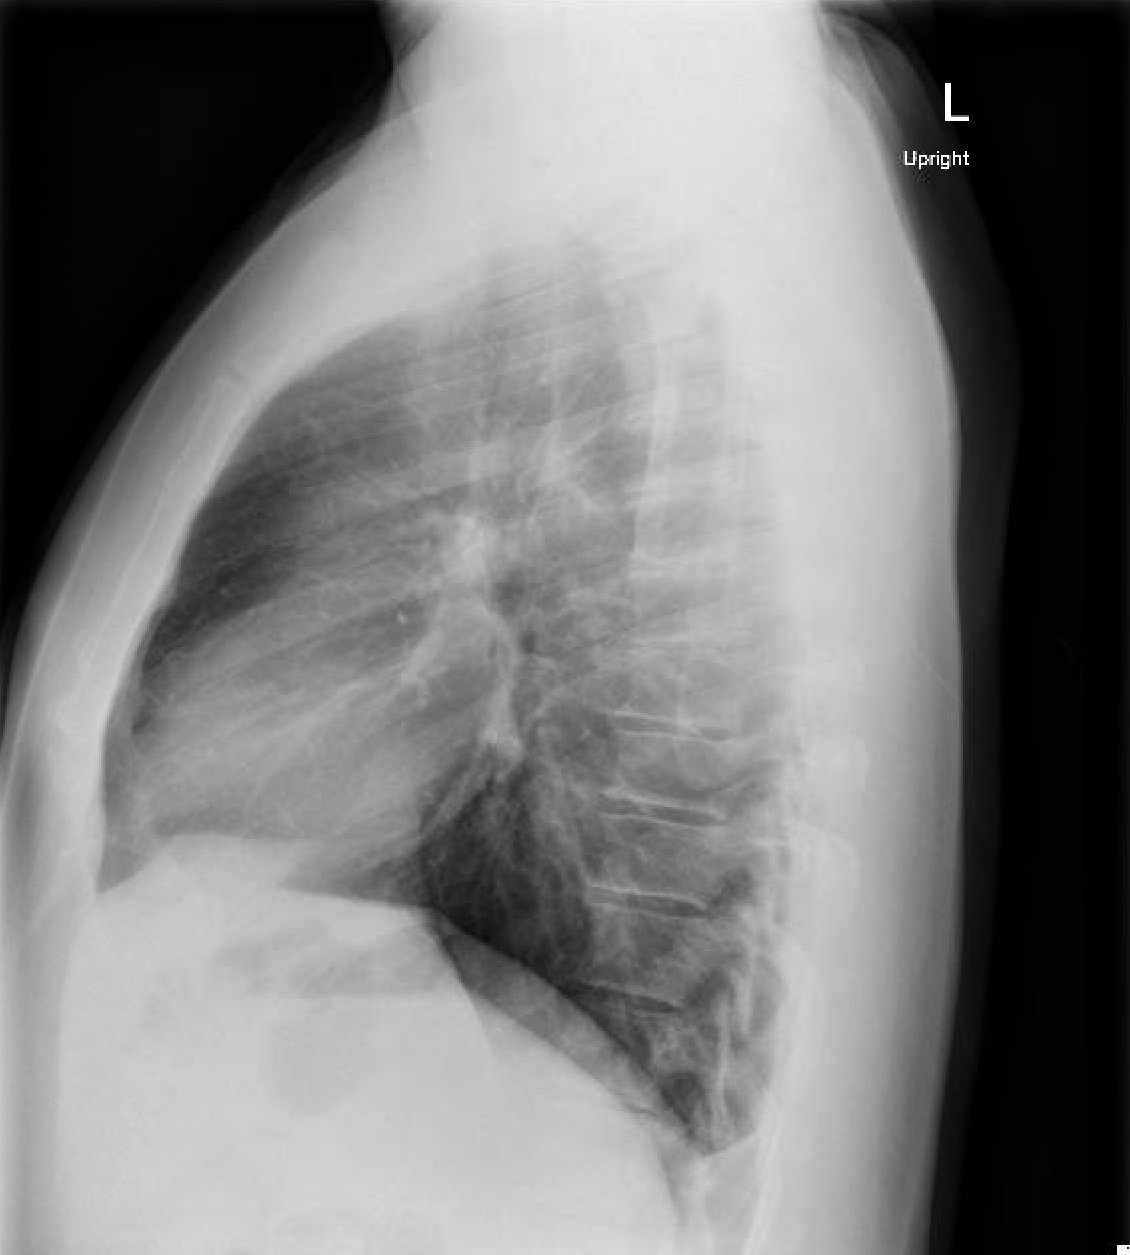

normal CXR lateral